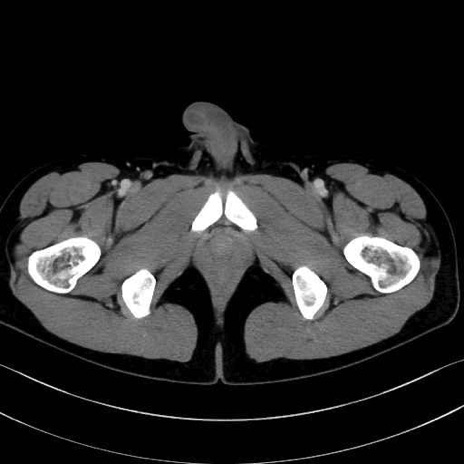

小殿筋 (Gluteus minimus)